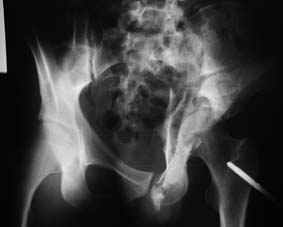

Это обзорные и косые снимки